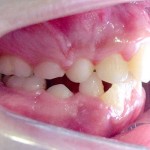

Este é um caso mais simples de se fazer e com um valor (custo-benefício) bastante cómodo.São somente 4 implantes na arcada inferior suportando uma barra sobre a qual será transferido em parte o esforço mastigatório. É confeccionada em RESINA como uma prótese total convencional.